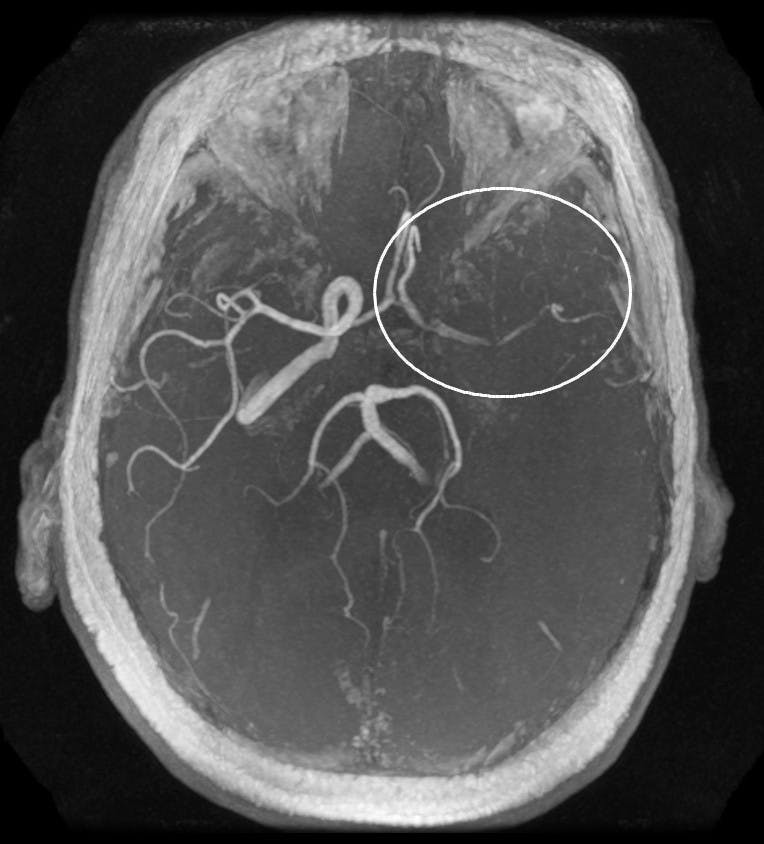

By Areeka Memon | March 15, 2016Ischemic stroke can occur when an artery that normally brings fresh blood from the heart and lungs to the brain is blocked.

Ischemic stroke can occur when an artery that normally brings fresh blood from the heart and lungs to the brain is blocked.